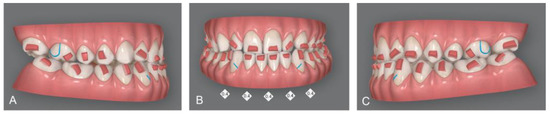

The orthodontic setup included the sequential staging of movements (Figure 3); the second molars were distalized first, and after 50% of their movement, the movement of the first molars began. The planned distalization was 2 mm on the right side and 1 mm on the left side. Once the distalization of the second molar was completed, the distalization of the second premolar began. In the same pattern, all the lower elements were distalized. A slight expansion of the upper and lower arches was necessary to allow the crowding to resolve. In addition, mild proclination of the upper anterior teeth was planned to create spaces distal to the upper lateral incisors.

Figure 3. Invisalign® (Align Technology, Tempe, AZ, USA) software staging table where it is possible to appreciate the “ladder” scheme of distalization. In the upper arch all teeth were moved at the same time. In the lower arch, lower teeth were distalized in a sequential way, while anterior teeth were moved from the beginning. Red triangles mean that all teeth had attachments.

Upon delivery of the first transparent aligners, rectangular retention attachments were applied to the posterior teeth and rectangular attachments with gingival bevels on the lower anterior teeth to ensure maximum retention of the aligners. In addition, posterior attachments provided the proper retention and control of molars and premolars distal tipping, while retention attachments on lower canines and upper first molars prevented side effect movements with the application of class III intermaxillary elastics. Interproximal reduction (IPR) between lower incisors of 2 mm was planned (Figure 4). After third molar extraction, composite attachments and metal buttons for elastic support were bonded. Orthodontic elastics plus clear aligners were delivered to the patient [22].

Figure 4. Invisalign® software display of attachments, programmed IPR and cuts for elastic: Right lateral vision of virtual setup (A); Frontal vision of virtual setup; IPR of 0.4 mm from canine to canine was planned (B); Left lateral vision of virtual setup (C).